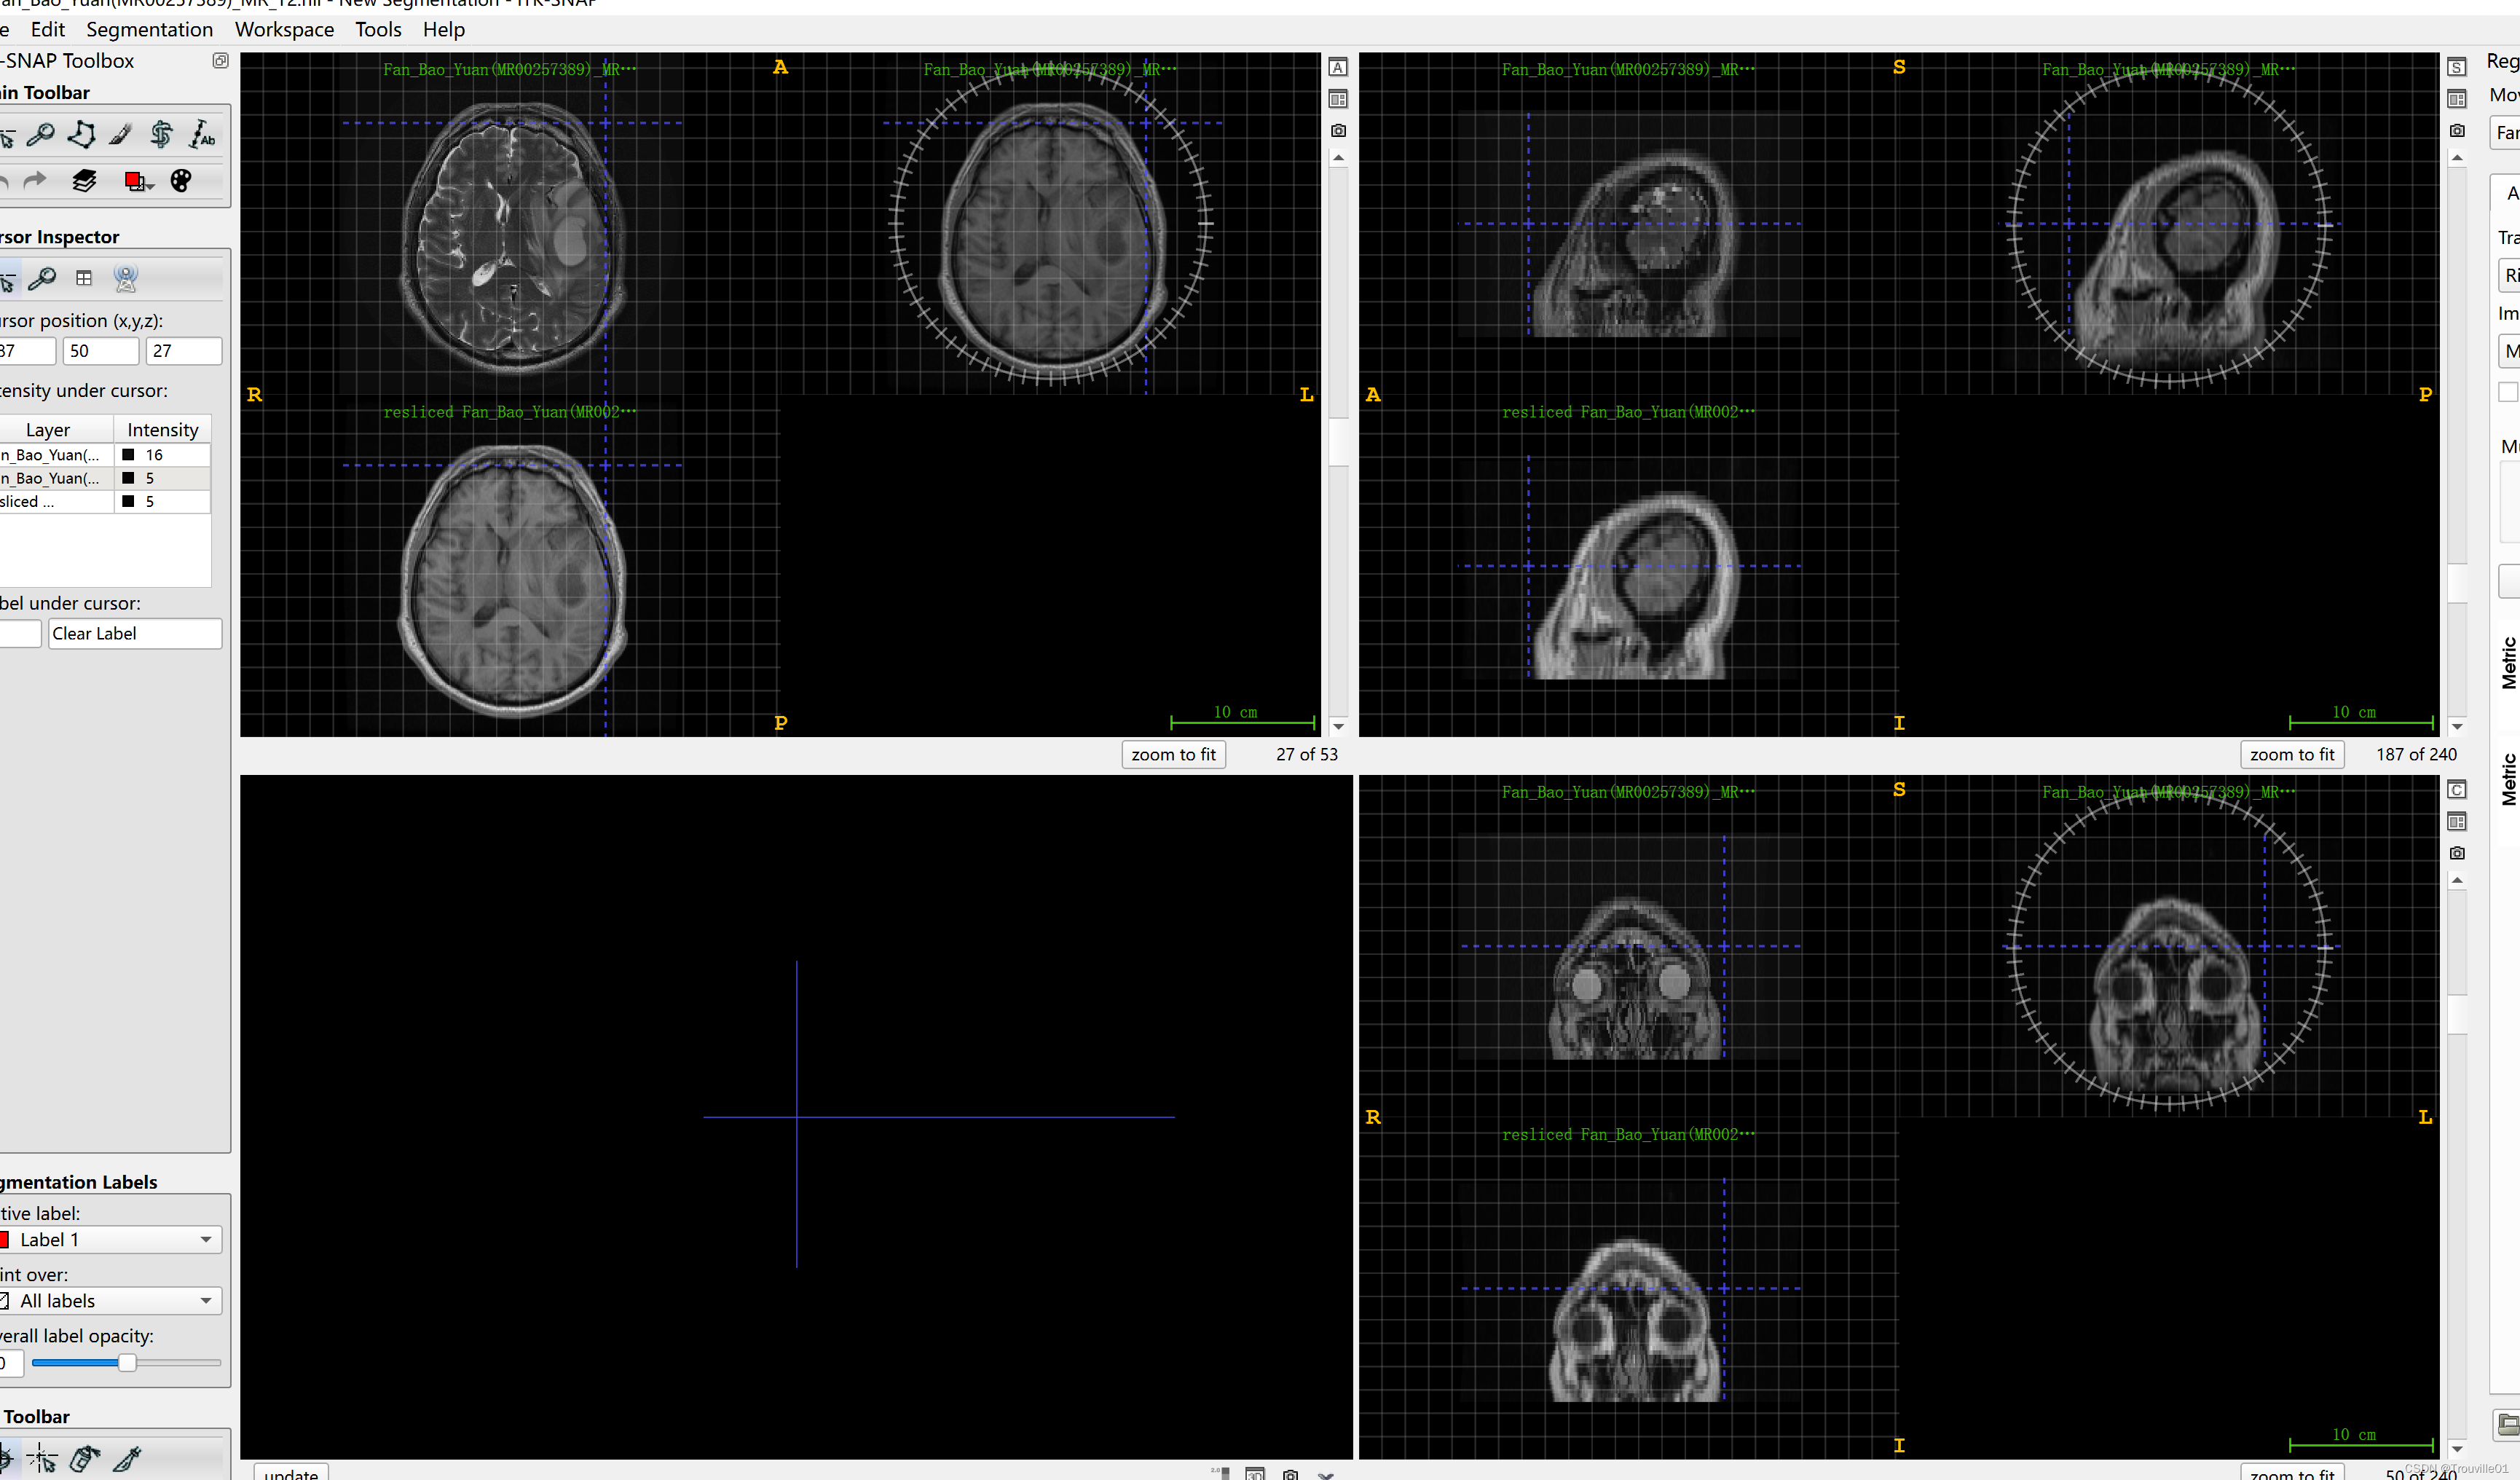

离close控件最近的那三个控件的最后一个,单击一下它,选择OK

7.保存配准后的图像,鼠标移到配准结果图像的右上角,会出现下拉按钮,点击会出现保存选项,点击保存即可!

ok,配准完成!其实这个教程更适合使用视频来讲解,后面有时间再弄。这个用软件来配准的,会很耗时,需要手动一个个弄,但可以手动来调整方向和对齐,比较适合难搞的图像配准任务!